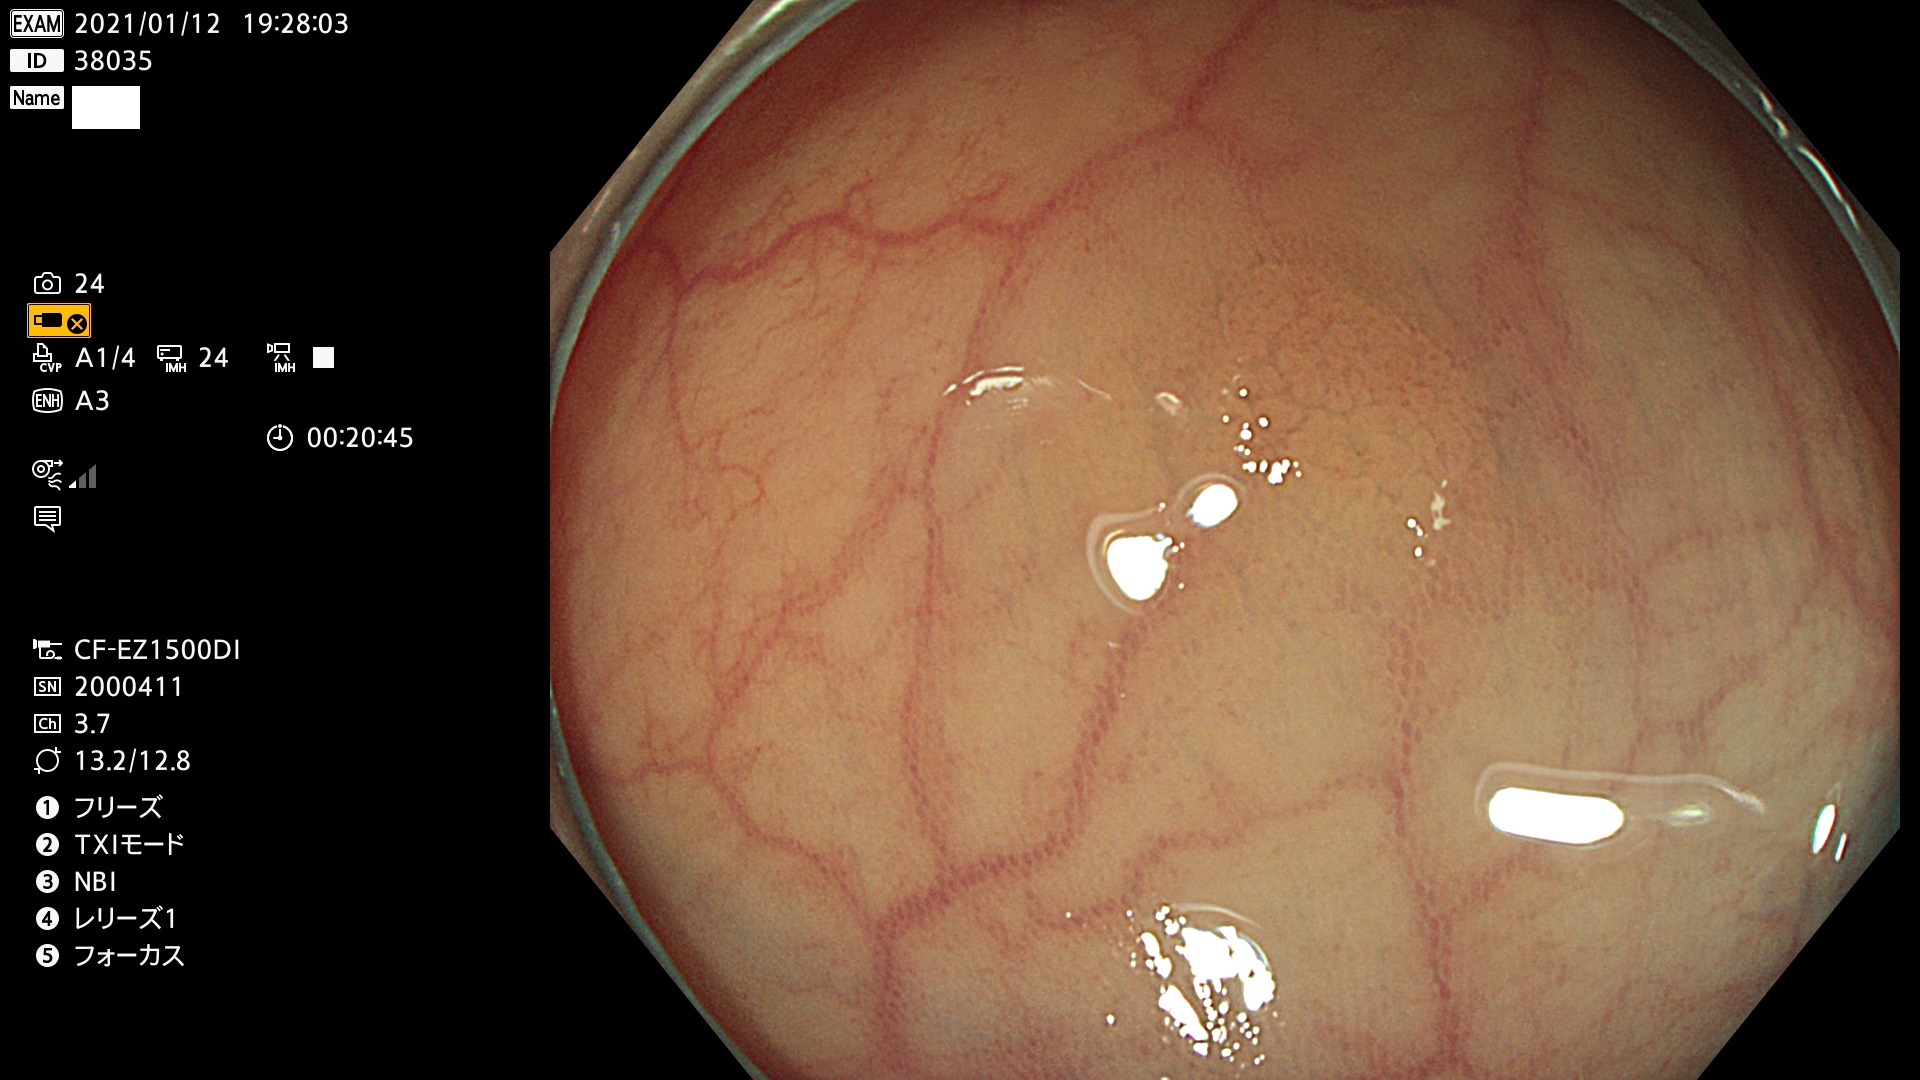

38001 38002 38003 38004 38006(SSAPのみ) 38007 38008 38009 38010 38012 38013 38014 38016 38018 38020 38021 38025 38026 38029 38032 38033 38034 38035 38036 38037(SSAPのみ) 38039 38043 38044 38048 38049 38050 38052 38055 38056 38057 38058 38059 38064(SSAPのみ) 38065 38068 38069 38070 38071 38072 38074 38075 38076 38078 38079 38080 38082 38083 38084 38085(SSAPのみ) 38086 38087 38088 38089 38090 38091 38092 38093 38094 38097 38098 38099

発見困難で危険性の高い平坦型病変(上記100名より抽出)